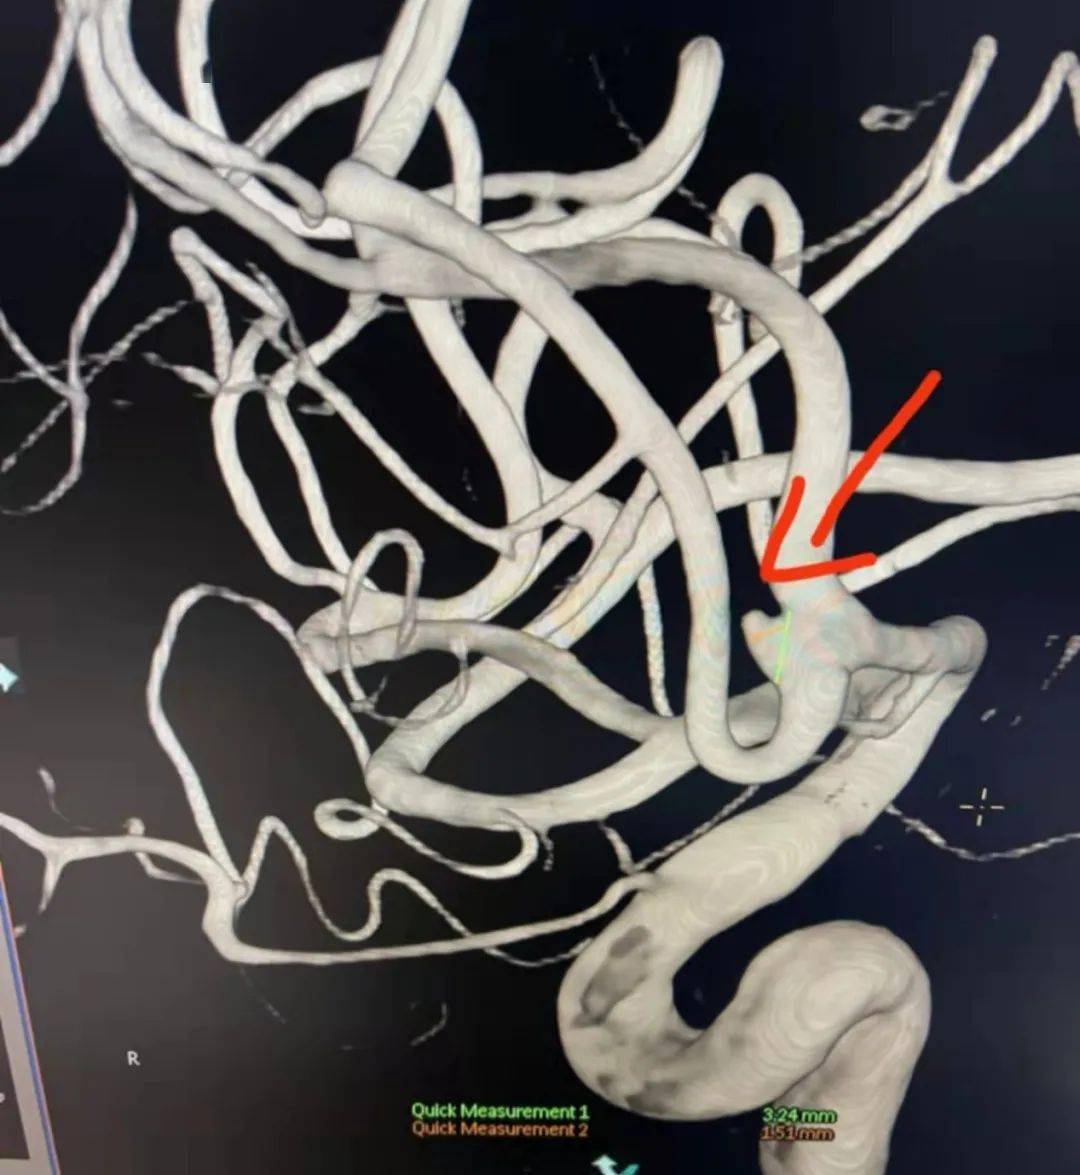

颈眼动脉多发动脉瘤的密网支架治疗